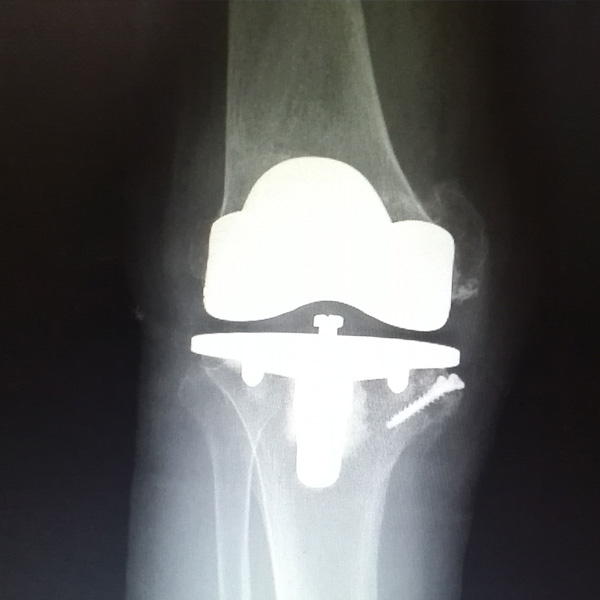

膝關(guān)節(jié)內(nèi)翻

患者劉某某,女66歲,左側(cè)膝關(guān)節(jié)嚴(yán)重內(nèi)翻(俗稱的“羅圈腿”),疼痛到不能生活自理。經(jīng)平臺(tái)推薦到哈爾濱醫(yī)科大學(xué)附屬第二醫(yī)院骨關(guān)節(jié)科就診,......